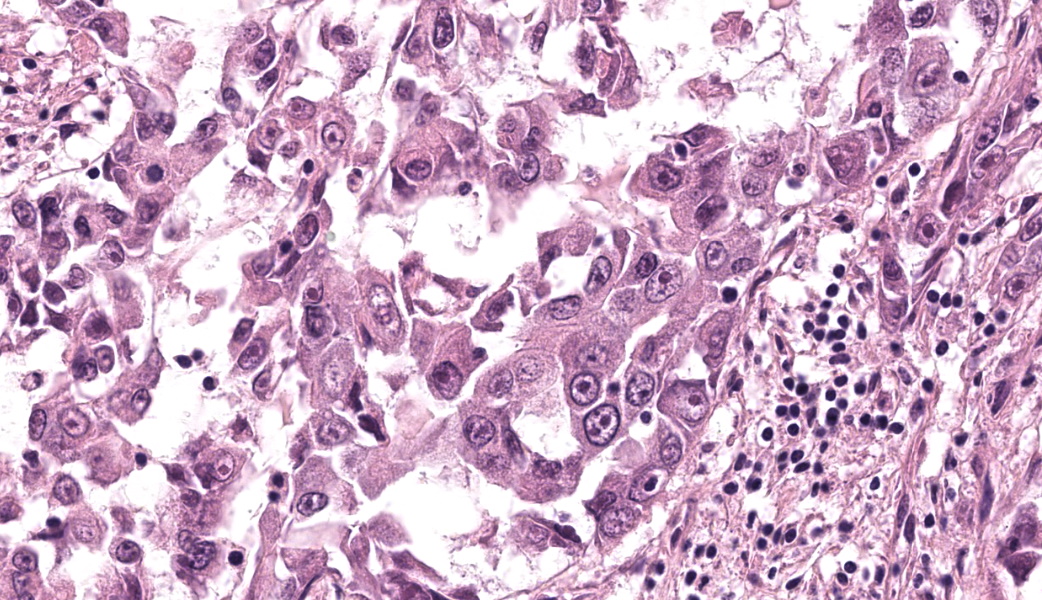

Microscopic Description:

Extending from and infiltrating the omentum is an unencapsulated, poorly demarcated, moderately cellular neoplasm composed of cuboidal to polygonal cells arranged in acini, tubules and nests, and more rarely micropapillary projections, on a moderate fibrovascular stroma. Neoplastic cells have variably distinct cell borders, an abundant amount of granular, eosinophilic and occasionally indistinctly vacuolated cytoplasm, and a pleomorphic, centrally placed nucleus with finely stippled to marginated chromatin and up to 3, occasionally very large distinct magenta nucleoli. There is marked anisocytosis and anisokaryosis, and 21 mitotic figures in 2.37mm2 – equivalent of 10 high power fields (40x obj); these are occasionally bizarre. There are occasional multinucleated neoplastic cells with up to 3 nuclei which occasionally compress and occasional apoptotic bodies are seen. Multifocally, neoplastic stroma contains minimal extravasations of erythrocytes (haemorrhage), and there are multifocal mild infiltrations of deform adjacent nuclei (nuclear molding).

There is occasional single cell necrosis, andmainly mature small lymphocytes, some plasma cells, and fewer neutrophils. Blood vessels are multifocally moderately congested and are often lined by plump (reactive) endothelium.

An interesting feature within the nuclei of some of the neoplastic cells caught the eye of a few of the participants. Infrequently, neoplastic mesothelial cells have what look like irregularly shaped, eosinophilic, intranuclear inclusion bodies (INIBs). This is an uncommon, but documented, feature of certain mesotheliomas in humans that can be seen both cytologically and histologically, particularly in adenomatoid and epithelioid forms.5,6 INIBs have also been seen, albeit rarely, in laboratory hamsters and rats infected with SV40 that subsequently developed mesothelioma.21 INIBs are reported, also rarely, in both cattle and dogs with mesothelioma associated with asbestos exposure, although the significance of those inclusions is unknown. Lastly, INIBs can be a rare feature of reactive mesothelial cells as well, making their presence challenging to interpret, but may prompt pathologists to assess for viral or asbestos-related causes.21